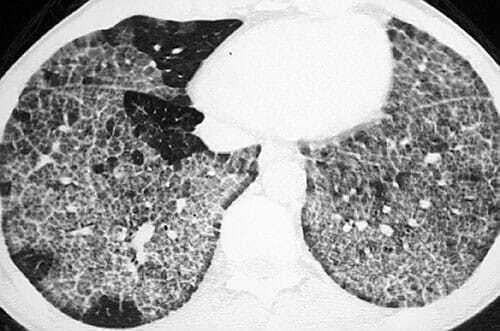

Usuário de Amiodarona + TC com Vidro Fosco + Bx com Foam Cells = …

A

Pneumonite Intersticial por Amiodarona

Geralmente após 6-12 meses de uso de Amiodarona.

Foam Cells = Macrófagos com Espuma. Tto: Suspender Amiodarona +/- Corticoide